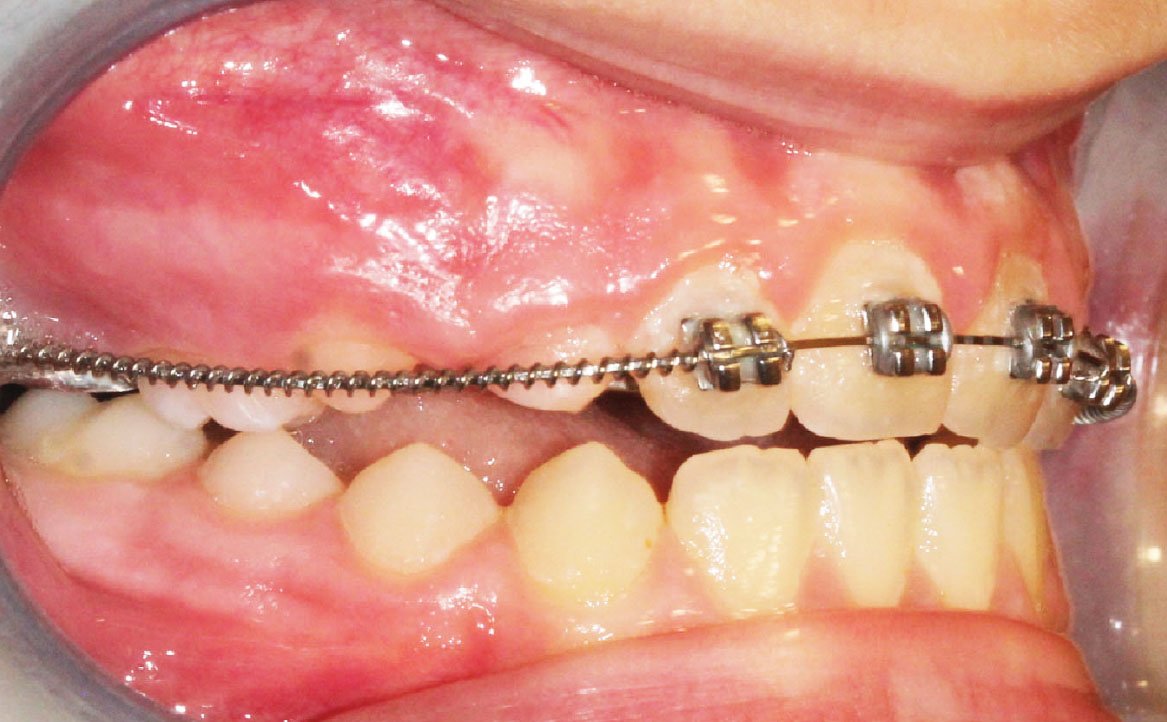

Bandaggio e sequenza archi

A tre mesi dalla cementazione dell’ERP si programma il bandaggio parziale superiore da 12 a 22 (Mini Master, prescrizione MBT, slot 22×28, American orthodontics) posizionando in maniera strategica i bk su 12 e 22, per il controllo del tip ed evitare interferenza con il tragitto eruttivo di 13 e 23. Sono state posizionate delle open coil attive e arco 016 Tanzo (fig. 8).

Fig. 8E Terapia intercettiva con REP e bandaggio parziale superiore.

Fig. 8D Terapia intercettiva con REP e bandaggio parziale superiore.

Al controllo successivo, a distanza di un mese, viene riattivata l’open coil e aumentati i rialzi occlusali già presenti.

A tre mesi dal bandaggio parziale viene inserito arco 016×22 Tanzo.

A 9 mesi dal montaggio dell’apparecchiatura overjet risulta positivo e gli elementi 13 e 23 sono in eruzione.

È ora assente lo shift anteriore (fig. 9).